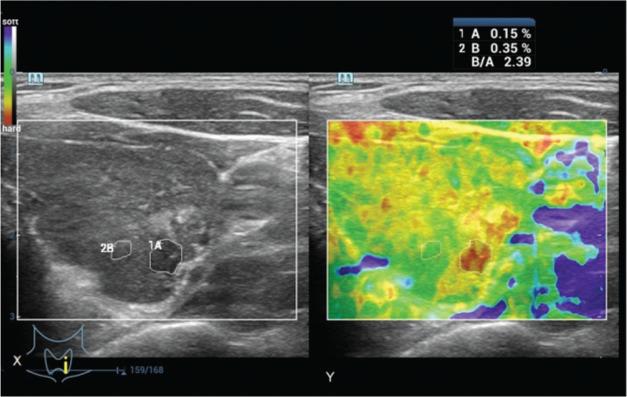

Fine-needle aspiration cytology is the risk stratification tool for thyroid nodules, and ultrasound elastography is not routinely used for the differential diagnosis of thyroid cancer. The current study aimed to compare the diagnostic parameters of ultrasound elastography and fine-needle aspiration cytology, using surgical pathology as the reference standard.

In total, 205 patients with abnormal thyroid function test results underwent ultrasound-guided fine-needle aspiration cytology on the basis of the American College of Radiology Thyroid Imaging-Reporting and Data System classification and strain ultrasound elastography according to the ASTERIA criteria. Histopathological examination of the surgical specimens was performed according to the 2017 World Health Organization classification system. Moreover, a beneficial score analysis for each modality was conducted.

Of 265 nodules, 212 measured ≥1 cm. The strain index value increased from benign to malignant nodules, and the presence of autoimmune thyroid diseases did not affect the results (p>0.05 for all categories). The sensitivities of histopathological examination, ultrasound elastography, and fine-needle aspiration cytology for detection of nodules measuring ≥1 cm were 1, 1, and 0.97, respectively. The working area for detecting nodule(s) in a single image was similar between strain ultrasound elastography and fine-needle aspiration cytology for highly and moderately suspicious nodules. However, for mildly suspicious, unsuspicious, and benign nodules, the working area for detecting nodule(s) in a single image was higher in strain ultrasound elastography than in fine-needle aspiration cytology.

Strain ultrasound elastography for highly and moderately suspicious nodules facilitated the detection of mildly suspicious, unsuspicious, and benign nodules.